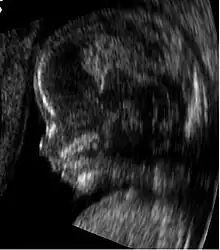

Obstetric ultrasonography, or prenatal ultrasound, is the use of medical ultrasonography in pregnancy, in which sound waves are used to create real-time visual images of the developing embryo or fetus in the uterus (womb). The procedure is a standard part of prenatal care in many countries, as it can provide a variety of information about the health of the mother, the timing and progress of the pregnancy, and the health and development of the embryo or fetus.

Traditional obstetric sonograms are done by placing a transducer on the abdomen of the pregnant woman. One variant, transvaginal sonography, is done with a probe placed in the woman's vagina. Transvaginal scans usually provide clearer pictures during early pregnancy and in obese women. Also used is Doppler sonography which detects the heartbeat of the fetus. Doppler sonography can be used to evaluate the pulsations in the fetal heart and bloods vessels for signs of abnormalities.[5]